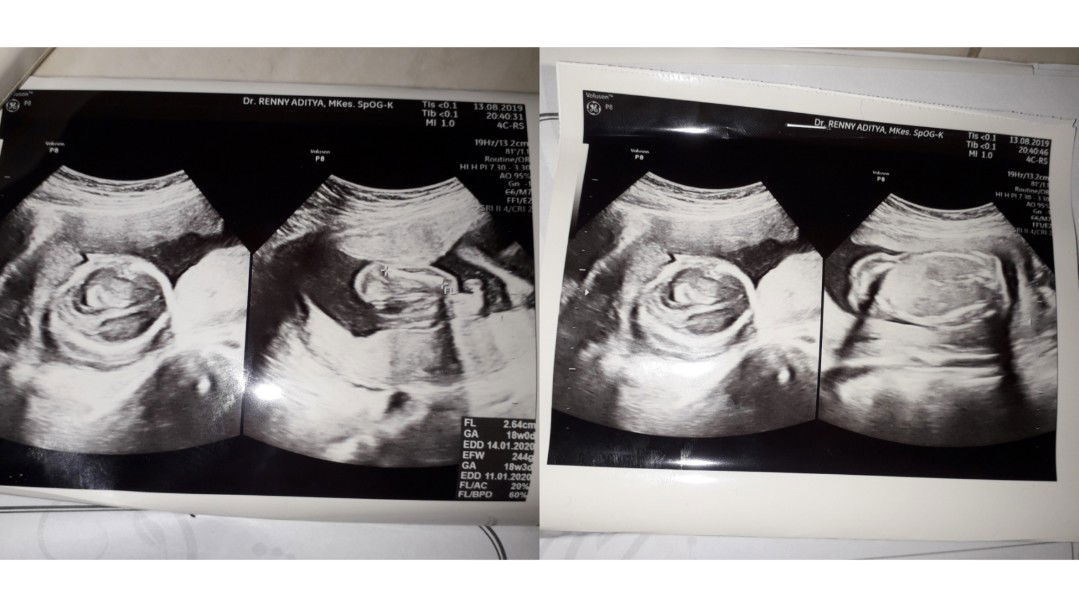

Yg tulisannya EFW bun

Efw 244g